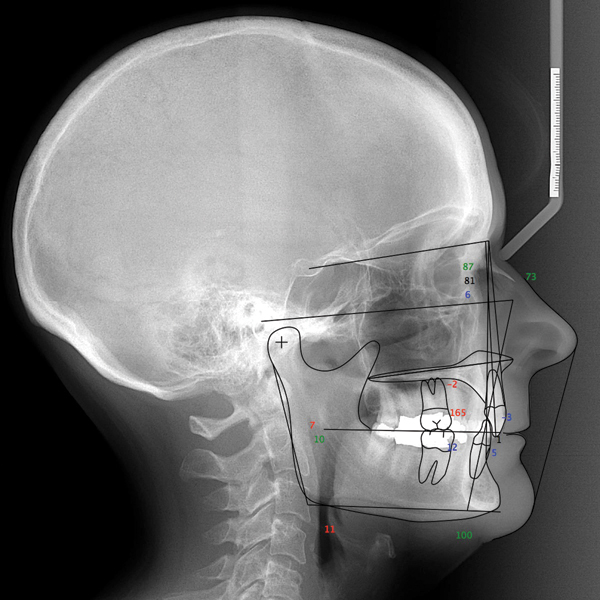

The Division 1 signifies that these hazardous gas or vapor air mixtures are. A morphologic and functional evaluation of Class II division 2 malocclusion based on digitized data from cephalometric and cinefluorographic radiography. Class ii division 2 degree Saturday March 12 2022 Edit.

Class ii division 2. The present study consists of 24 subjects who had Class II division 2 malocclusion Stage 6 of Hassel and Farman cervical maturity indicator and post-treatment. Similar to Type 1 with the addition of drip shields Type 2 provides a degree of protection against limited amounts of dirt and light exposure to water like dripping or.